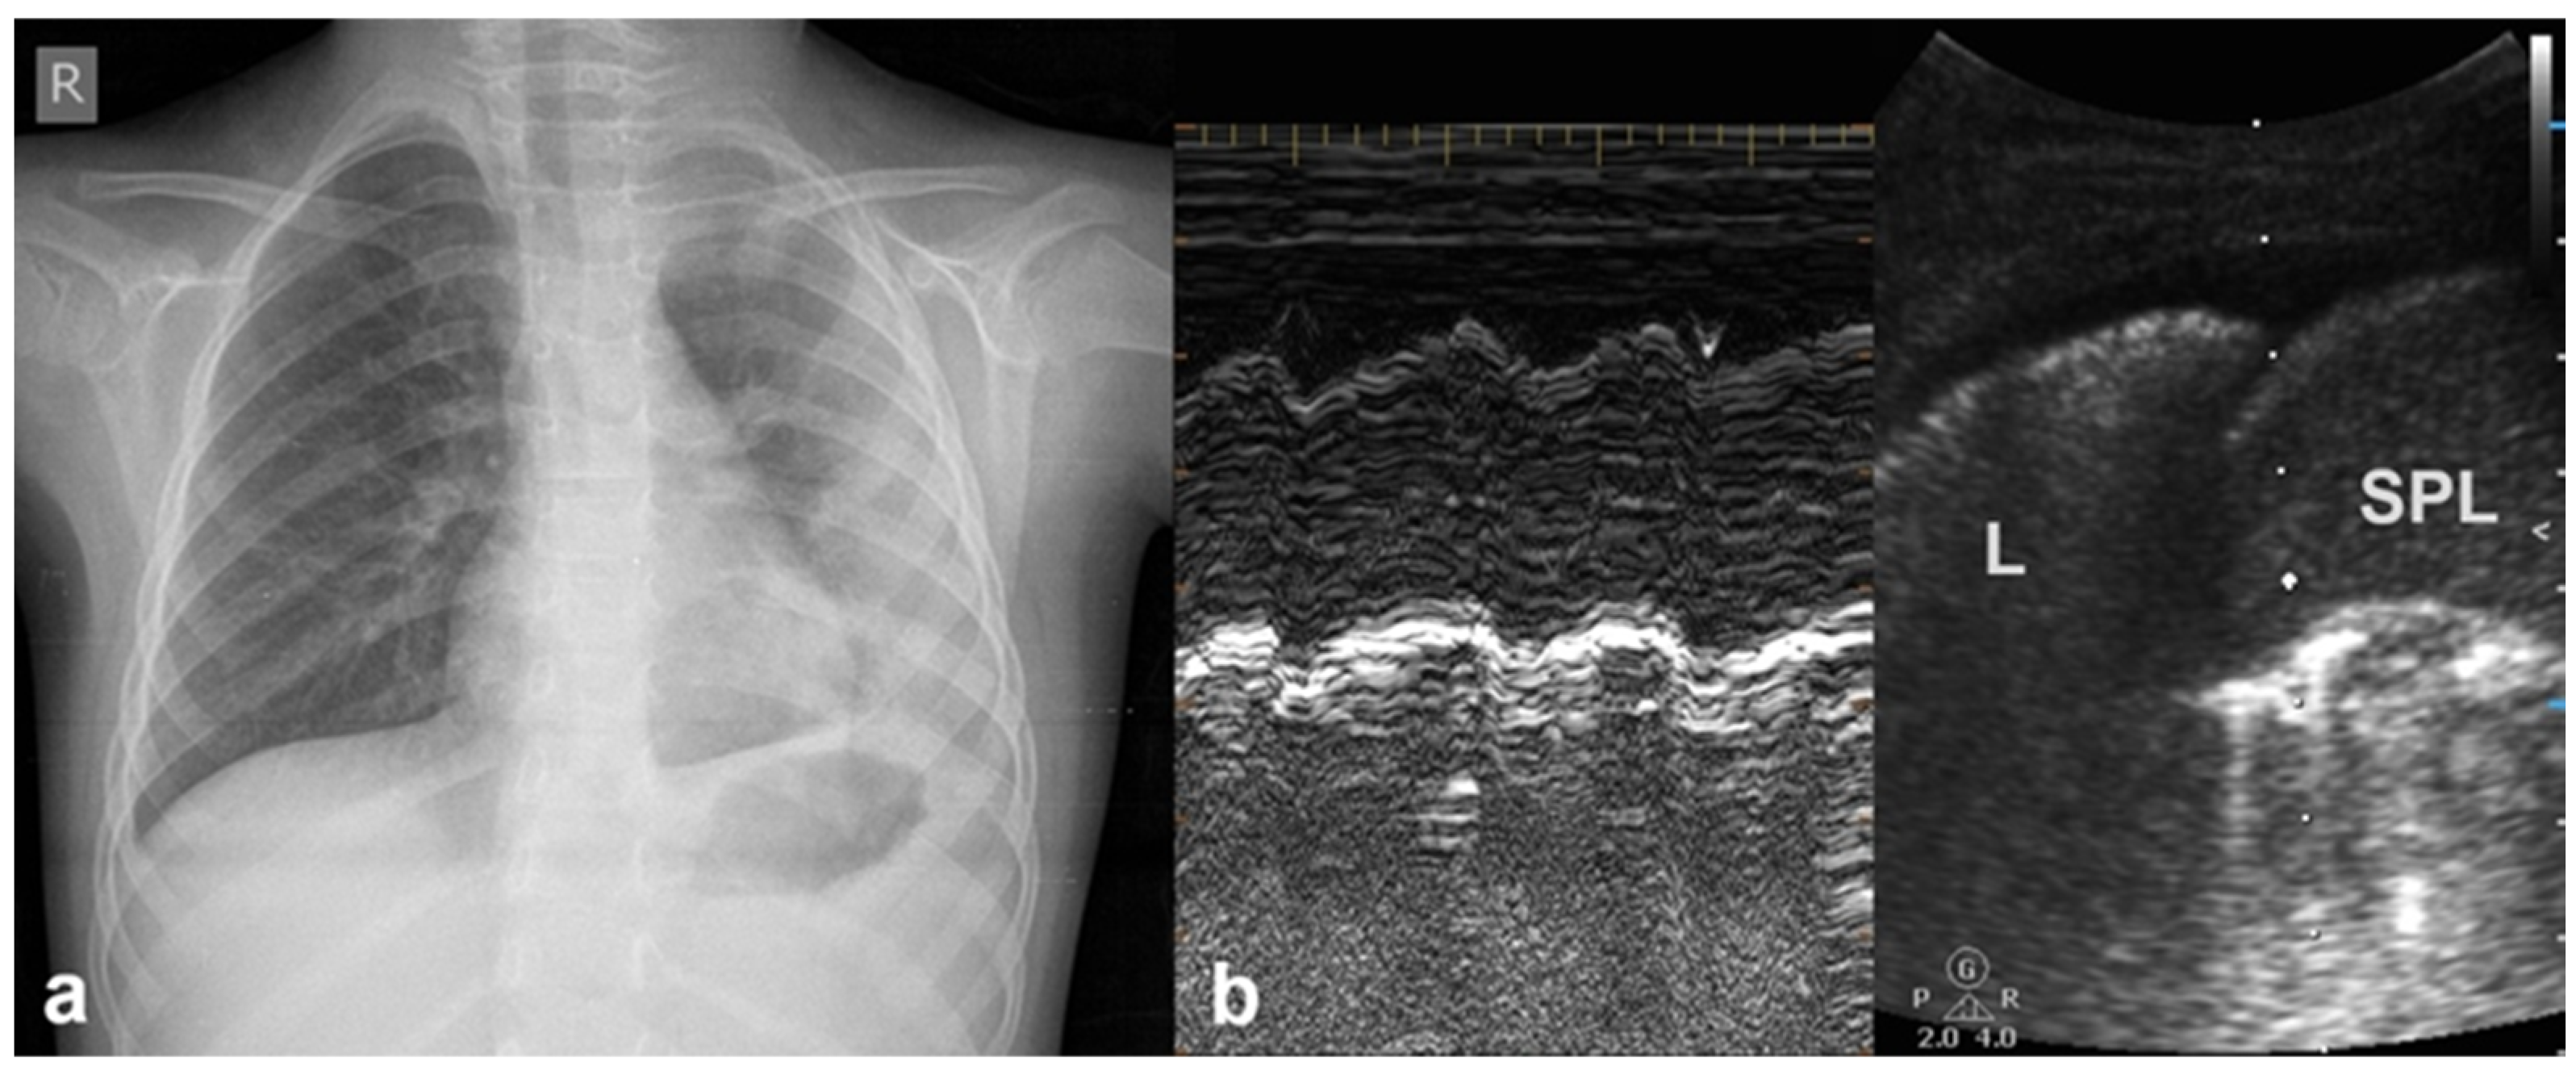

3.1.6. Sinusoid Sign

In cases of pleural effusion, the accumulation of fluid between the pleural layers causes separation of the visceral and parietal pleura. LUS assessment of this condition in M-mode is associated with the presence of a characteristic sinusoidal pattern, resulting from the cyclical movement of the lung line toward the pleural line during inhalation and away from the pleural line during exhalation. The presence of this “sinusoid sign” indicates the presence of low-viscosity fluid within the pleural space, separating the visceral and parietal pleura. This finding can assist in differentiating pleural effusion from pleural thickening, as its presence is indicative of mobile, free-flowing fluid typically associated with pleural effusions (Figure 7) [17].

Figure 7.

Sinusoid sign: (a) CXR: left-sided consolidation (is there any pleural effusion?). (b) LUS reveals fluid, a finding based on the sinusoid sign, with a characteristic sinusoidal pattern due to the cyclical movement of the lung line toward the pleural line during inhalation and away from the pleural line during exhalation (L: lung; SPL: spleen).